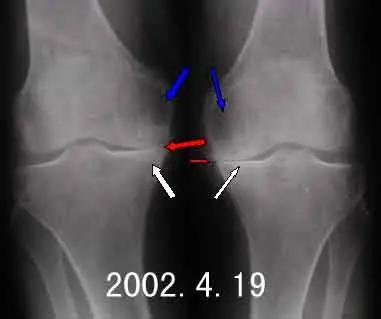

2、 截骨畸形矫正术:主要适用于关节退变程度轻,但关节 内翻或外翻畸 形明显的病人,这样的病人通过截骨矫正畸形,恢复关节正常的负重后疼痛会随之减轻。